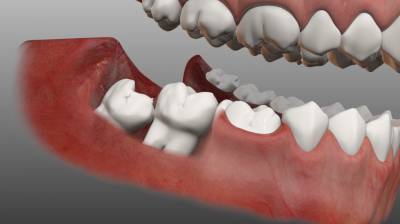

Зуб мудрости – 8-й зуб в ряду, или 3-й моляр. Он прорезается позже остальных, чаще всего в возрасте 20 – 23 лет.

Этот зуб является рудиментом, доставшимся людям от предков, челюсть которых была значительно шире.

Поэтому восьмёрки, так называют в просторечие зубы мудрости, вызывают много проблем при прорезывании. Часто они имеют неправильное направление роста, что приводит к их удалению, но такая операция никогда не бывает простой.

Если зуб мудрости прорезался не полностью, или его положение неверно по отношению к другим зубам (восьмёрка может расти в щёку или в соседний зуб), его называют ретинированным зубом. В таком случае операция по удалению может оказаться особенно сложной, и иметь неприятные последствия: